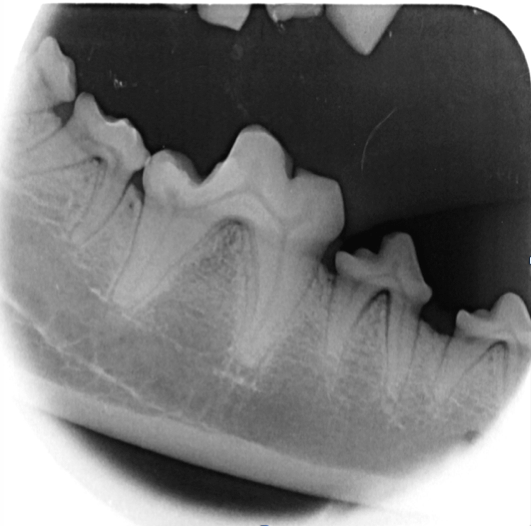

In Narkose sah man auf Leilas Röntgenbildern dann das gesamte Ausmaß ihrer Zahnerkrankung. Bis auf die Canini wiesen alle Zähne hochgradige Wurzelentzündungen mit Osteolysen des Kieferknochens auf. Deshalb konnte man auch schon von außen die Zahnhälse freiliegend sehen. Im Wurzelbereich waren die Veränderungen so schlimm, dass der Unterkiefer kurz vor einer Fraktur stand.

Solche Veränderungen treten oft bei einer hochgradigen Parodontitis auf. Eine Parodontitis ist die Entzündung des gesamten Zahnhalteapparates (also des Kieferknochens, des Zements, der Paradontalfasern und des Zahnfleischs) und wird durch die Bakterien, welche im Plaque enthalten sind, hervorgerufen. Diese zerstören die Anheftung der Gingiva am Zahn, und die Bakterien können bis zur Wurzel vordringen. Hier rufen sie Entzündungsreaktionen des Kieferknochens und der Gingiva hervor, wodurch beide sich zurückziehen und tiefe Paradontaltaschen entstehen lassen. Doch Leila hatte, wie auf den Bildern schön zu sehen ist, kaum Zahnstein oder Plaque.

Es ist sehr wichtig zu verstehen, dass eine Zahnreinigung ohne Aufnahme eines kompletten Zahnstatus inklusive Zahnröntgen nichts weiter ist als eine kosmetische Behandlung, da krankhafte Prozesse übersehen werden (abb. 7-10).